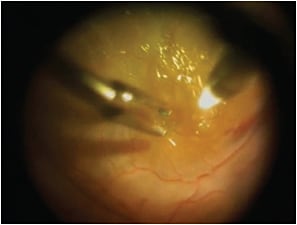

Comparing the failure rates with different treatment methods allowed the study authors to provide recommendations based on RD etiology. Pneumatic retinopexy or scleral buckling (Figure 3) was useful in cases in which a superior atrophic hole induced retinal detachment. However, in the presence of a flap tear, the treatment of choice is scleral buckling, with a lower failure rate than both pneumatic retinopexy and vitrectomy.

Figure 3. A) Intraoperative view during scleral buckling of early onset retinal detachment without PVR. B) Scleral sutures during scleral buckling as seen intraoperatively with a slit lamp.